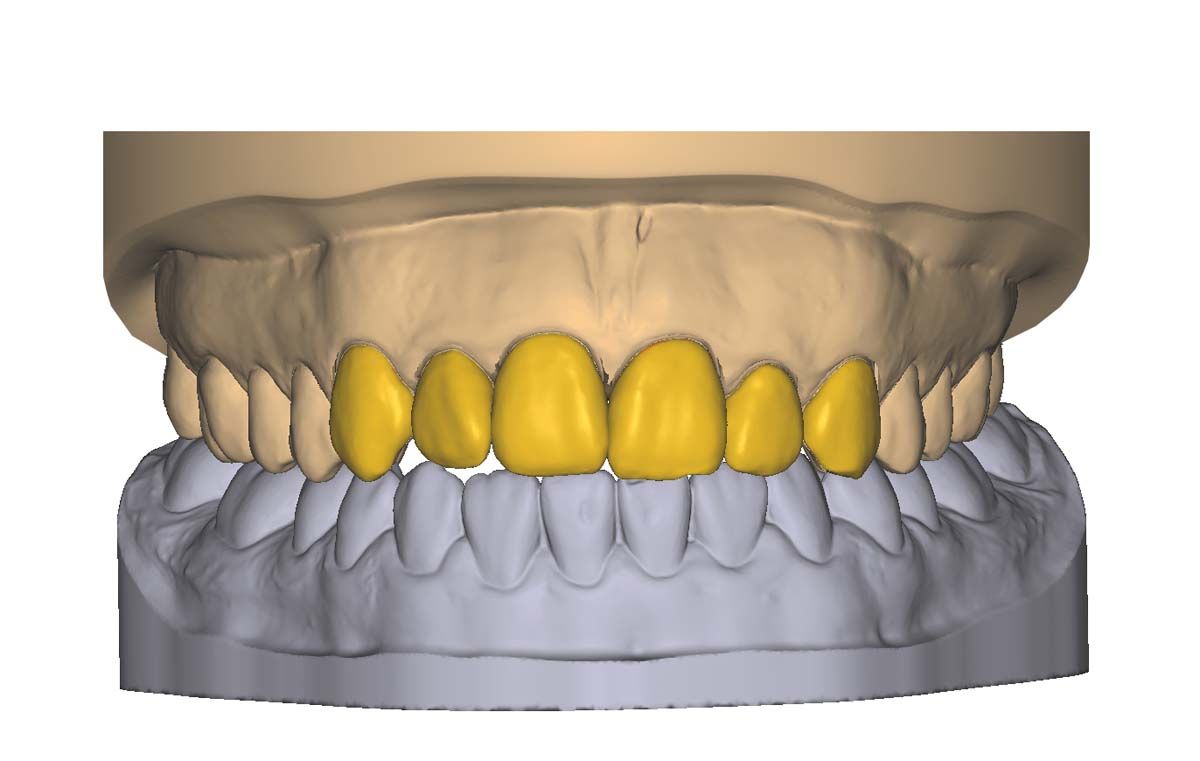

We used to try showing patients their clinical situation on 2D x-rays and demonstrating treatment using models. Later, digital intraoral cameras helped, but they could not show much more than what a patient could see in a mirror. Today, it is possible to show patients every angle of their clinical situation in hyperrealistic 3D with a CBCT scan. Now, when I recommend treatment to patients and they ask why, I am armed with an interactive image captured by my CS 8200 3D extraoral imaging system (Carestream Dental). I scroll through the tooth and bone, point out lesions below the surface, and show why there is or is not enough bone for an implant. If you use something like the Prosthetic-Driven Implant Planning module to automatically merge an intraoral scanner file with the CBCT scan, you create an even more accurate picture. How much easier is it for the patient to accept treatment when they are seeing the end results of that treatment?